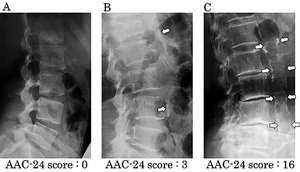

FIG 1 ACC-24 scoring system from the Framington Heart Study.

Here's how it works: On a lateral lumbar film, trace the aorta from L1 through L4, both the anterior and posterior margins. Score the amount of calcification as follows:

- 0: no aortic calcific deposits

- 1: small scattered calcific deposits filling less than one-third of the longitudinal wall of the aorta

- 2: one-third or more, but less than two-thirds of the longitudinal wall of the aorta calcified

- 3: two-thirds or more of the longitudinal wall of the aorta calcified

These scores are tallied for each vertebral level L1-L4; both at the anterior and posterior wall of the aorta. Add up the number from at all levels including anterior and posterior; that is the score. Sounds crude and simple, but it is inexpensive and works well. Minimum score is 0 and maximum is 24.7 The AAC-24 score actually also correlates well with carotid artery atherosclerosis.8 The higher the score, the higher the incidence of cardiovascular disease elsewhere.